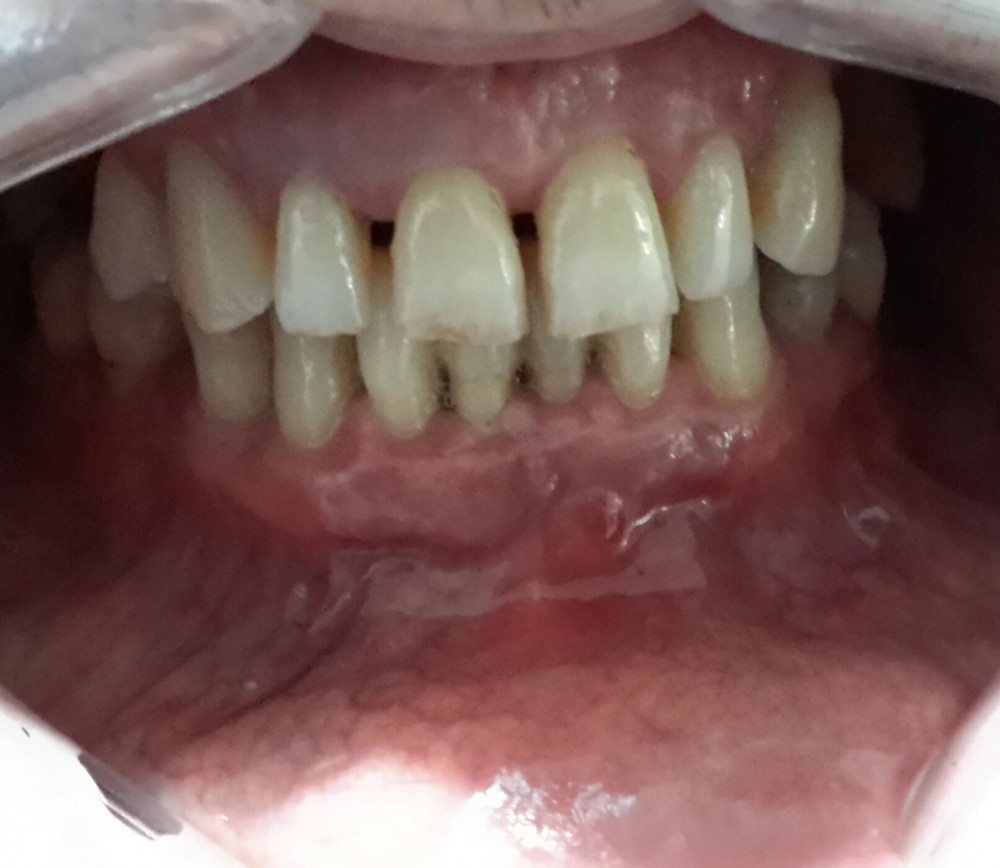

Pacient in varsta de 39 de ani s-a prezentat la Cabinetul stomatologic Jollydent speriat de faptul ca dintii frontali inferiori prezentau un grad mare de mobilitate.

In urma evaluarii clinice si radiologice si de comun acord cu pacientul am hotarat sa facem imobilizare cu banda din fibra de sticla si laserterapie.

1.Igienizare: - indepartarea tartrului supragingival prin detartraj cu ultrasunete si periaj profesional.

2.Imobilizarea dintilor mobili cu banda din fibra de sticla.